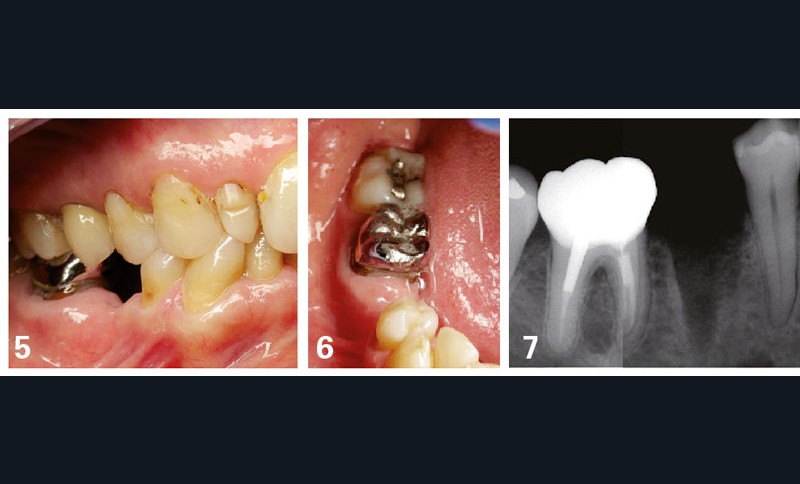

Dans le cas exposé figures 5 à 7, le traitement prothétique proposé pour remplacer la 45 peut être la couronne sur implant ou le bridge traditionnel 44-[45]-46. Cette dernière solution est moins favorable, sur le plan de la conservation tissulaire, que la solution implantaire. Le devoir de conseil du chirurgien-dentiste va donc naturellement l’amener à conseiller le patient en faveur de cette solution implantaire (tableau 2).

Dans le cas où une contre-indication formelle interdit le recours à l’implant (affection systémique, par exemple), la solution du bridge peut être proposée.

Le raisonnement suit alors l’exemple précédent, avec une possibilité pour le bridge métallique : une préparation a minima (économie tissulaire de 44) et, surtout, la volonté du patient satisfait de la présence de la couronne métallique sur 46 sans aucune complication.